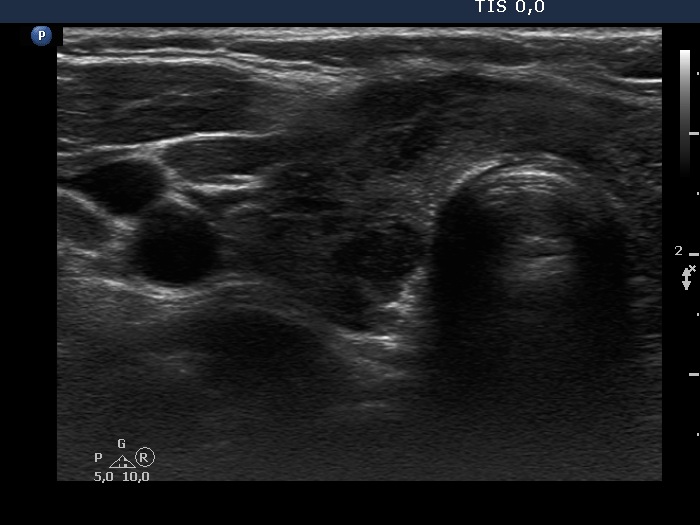

Benign Hashimoto's thyroiditis (cytological diagnosis) - case 1251

First, we demonstrate two cases of Hashimoto's thyroiditis with pronounced fibrotic changes. Both present pale and bright hyperechogenic granules and lines corresponding to normal and excessive connective tissue. Neither of the discrete areas are nodules in a pathological sense.